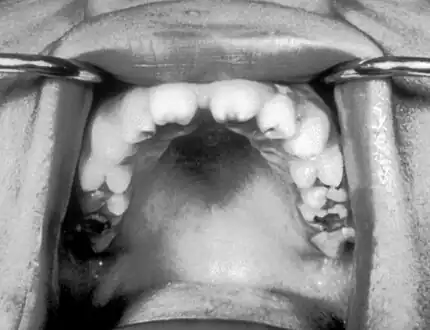

| Notched incisors in congenital syphilis | |

Hutchinson's teeth are small teeth with notches on their biting surfaces, seen in congenital syphilis.[1]

Hutchinson's teeth (and palatal perforation )

Notched incisors known as Hutchinson's teeth which are characteristic of congenital syphilis